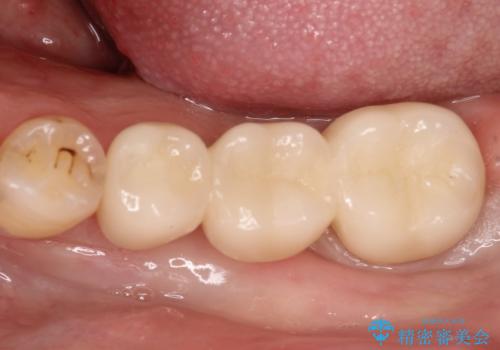

奥歯で噛めるようになりたい。オールセラミッククラウンブリッジ

今回はブリッジでの補綴を希望されたため、オールセラミッククラウンにより治療を行っております。

今回は両隣在歯に修復治療が行われており、外科治療を伴わないブリッジにて修復を希望され治療を行っております。